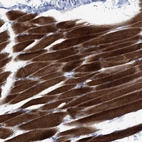

Immunohistochemical staining of human skeletal muscle shows strong cytoplasmic positivity in myocytes.